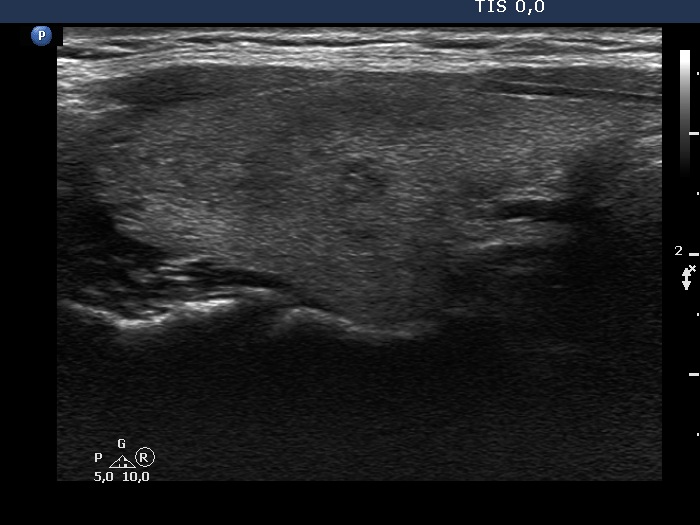

Subacute granulomatous thyroiditis - case 264

Two years after the first visit (ultrasonographic picture 2)

Right lobe, longitudinal scan. This image reveals other hypoechoic areas with ill-defined borders.